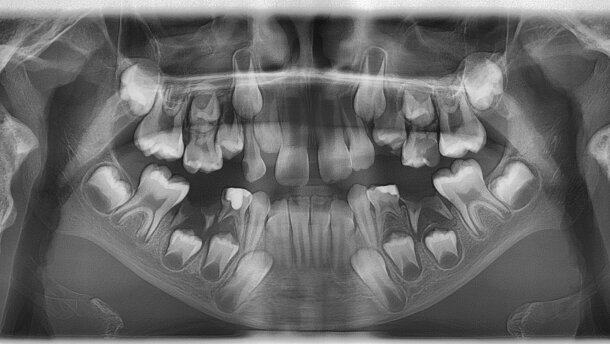

Najbliższa przyszłość to całkowite odejście od rejestracji zdjęć rtg na nośnikach analogowych i przejście na radiografię cyfrową w gabinetach stomatologicznych ze względu na przewagę cyfrowych systemów obrazowania nad filmami rentgenowskimi.

Do zalet radiografii cyfrowej należy redukcja dawki promieniowania rentgenowskiego koniecznej do otrzymania zdjęcia, wysoka rozdzielczość obrazu, możliwość regulacji kontrastu i jasności radiogramu czy zastosowania filtrów, pozwalająca na dopasowanie parametrów zdjęcia do potrzeb diagnostycznych (ocena próchnicy, choroby przyzębia brzeżnego itp.), a także dysponowanie więcej niż jedną kopią zdjęcia (dla pacjenta, dla lekarza, do archiwum, do konsultacji).

Być może z czasem, w związku z obserwowaną redukcją dawki promieniowania rentgenowskiego koniecznej do zarejestrowania tomografii stożkowej, badania CBCT całkowicie zastąpią zdjęcia pantomograficzne, które są podatne na błędy techniczne, trudne do analizy oraz nie przedstawiają wszystkich struktur w obrębie części twarzowej czaszki, a jedynie te objęte obrazowaną warstwą.